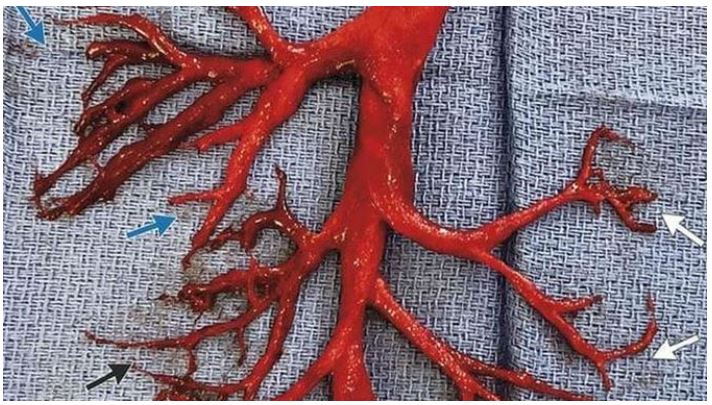

越来越多的证据证明,完全接种了武汉冠状病毒(COVID-19)疫苗并得到加强的人正在因血管系统中形成血凝块而死亡。更多的人需要大声反对疫苗